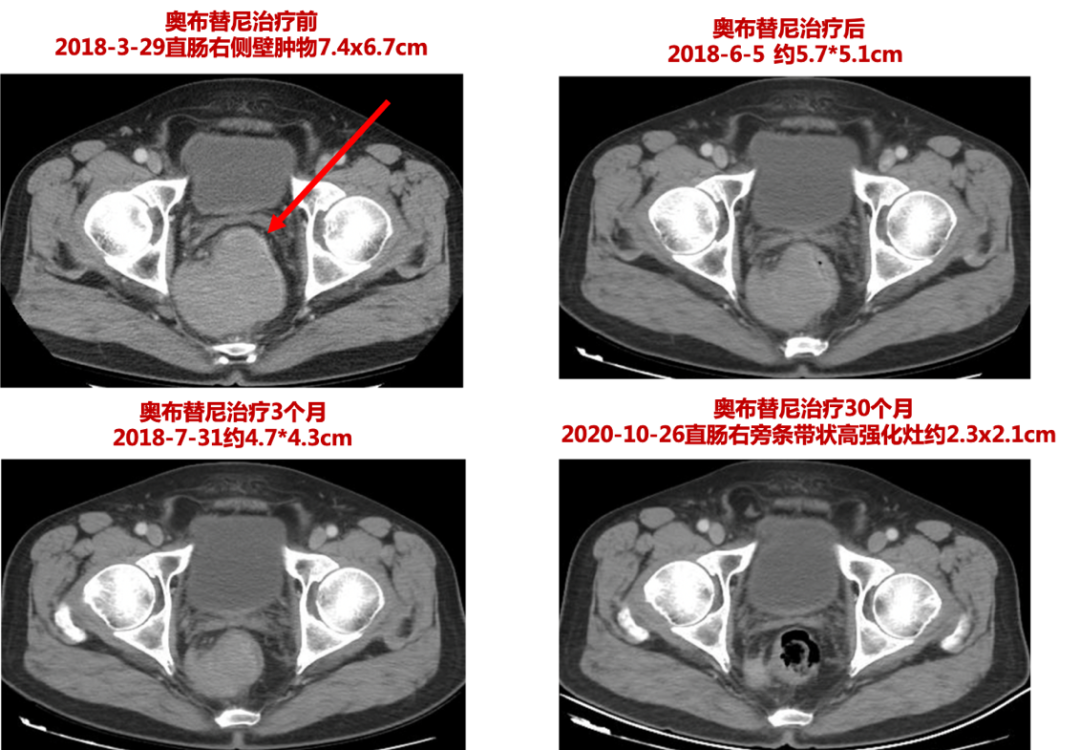

邓丽娟教授:在我科应用奥布替尼治疗的患者中,有一位患者令我印象深刻。患者是一位67岁的老年男性的套细胞淋巴瘤患者。患者2015 年在我科接受了R-CHOP/R-Ara-C交替方案化疗共6周期,6周期后评效为 CR,因年龄原因未行ASCT巩固,也未行利妥昔单抗维持治疗,治疗结束后定期复查无异常。2017年10月患者新出现便中带血,复查肠镜及 PET-CT显示淋巴瘤复发,直肠肿物约7cm*8cm,伴盆腔淋巴结受累,当时血红蛋白120g/L,为轻度贫血。患者疾病复发后顺利入组 ICP-022,即奥布替尼治疗复发难治套细胞淋巴瘤的临床试验, 入组前诊断为:非霍奇金淋巴瘤复发,II期A,套细胞淋巴瘤,侵及直肠,侵及直肠周围及盆腔多发淋巴结;消化道出血;HBV既往感染。患者于2018-4-12 起开始接受奥布替尼 150mg qd治疗,服药1周后便血完全缓解。定期监测患者血常规,血红蛋白恢复至140g/L。服药 3个月时,影像学检查提示患者直肠肿物明显缩小(图1)。

至今该患者已服药2年7月,直肠肿物仅约2cm,疾病维持 PR(图1)。服药期间,患者仅发生一过性WBC 减低1级,ALT 升高 1 级,均自行恢复正常。用药过程中,我们监测患者的 HBV-DNA 均正常。无其它AE发生。这例患者的治疗过程提示,奥布替尼的有效性、安全性和耐受性都非常好。

图1.奥布替尼临床应用病例分享——直肠病灶CT变化